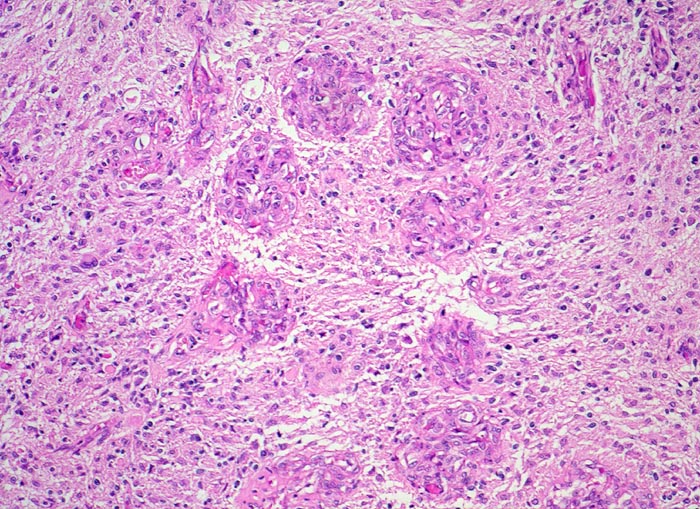

PathoPic ID 5202 - Glioblastoma multiforme (WHO IV)

Glioblastoma multiforme (WHO IV)

maligner Tumor

Hirn temporal

Nervensystem

Für das Glioblastom typische zu einer Kette angeordnete glomerulumartige

Gefässknäuel.

Seit zwei Monaten zunehmende Persönlichkeitsveränderungen, Kopfschmerzen und progrediente fokal neurologische Zeichen.

Histologie

100

52